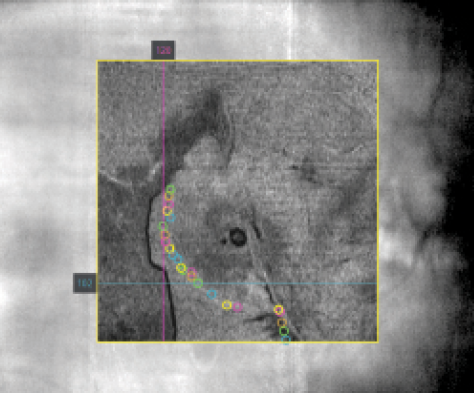

Figure 5. Projection of vitreomacular traction in an LSO image of the macula. Marked points represent adaptation borders of the vitreous to the macula. Black pixels represent elevated membrane borders (GapMap).

Another interesting potential application of computer-assisted retinal surgery is the identification and intraoperative projection of landmarks. For instance, vitreomacular traction borders could be identified and marked on OCT scans using points and lines, respectively (Figure 5). Projecting these landmarks onto intraoperative retinal scans could help the surgeon to detach the vitreous from the macula in a more controlled, less traumatic manner by cutting around the vitreous and peeling it carefully using the aspiration mode of the cutter or forceps.